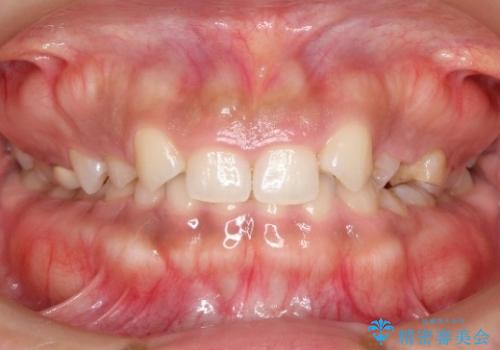

[ 歯周病・矯正・セラミック治療 ] 1つの医院で行う包括的歯科治療

担当医 大元洋佑